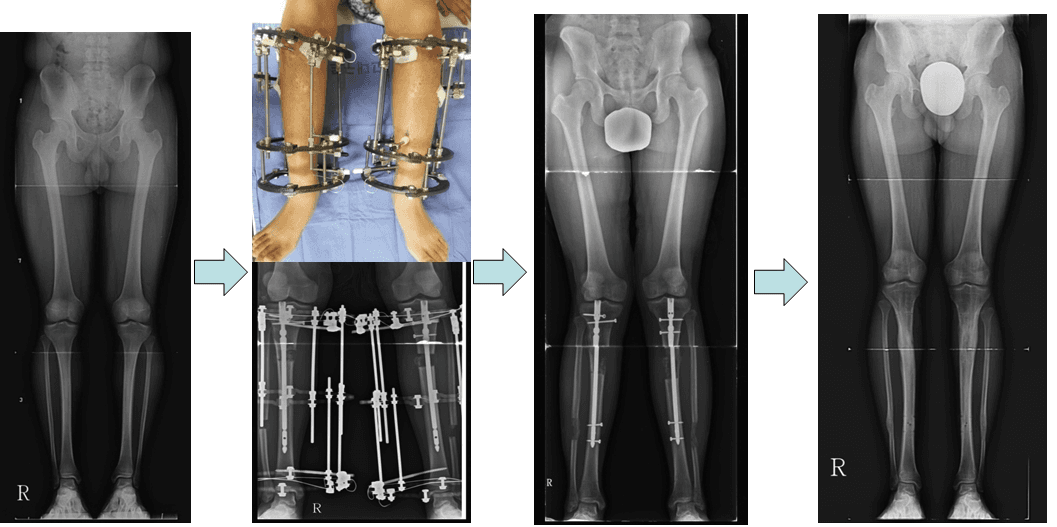

A patient with short stature and no other underlying conditions who has lengthened their calf bones by approximately 10 centimeters.

A short patient without any disease. Height was increased about 10 cm by lengthening tibia.